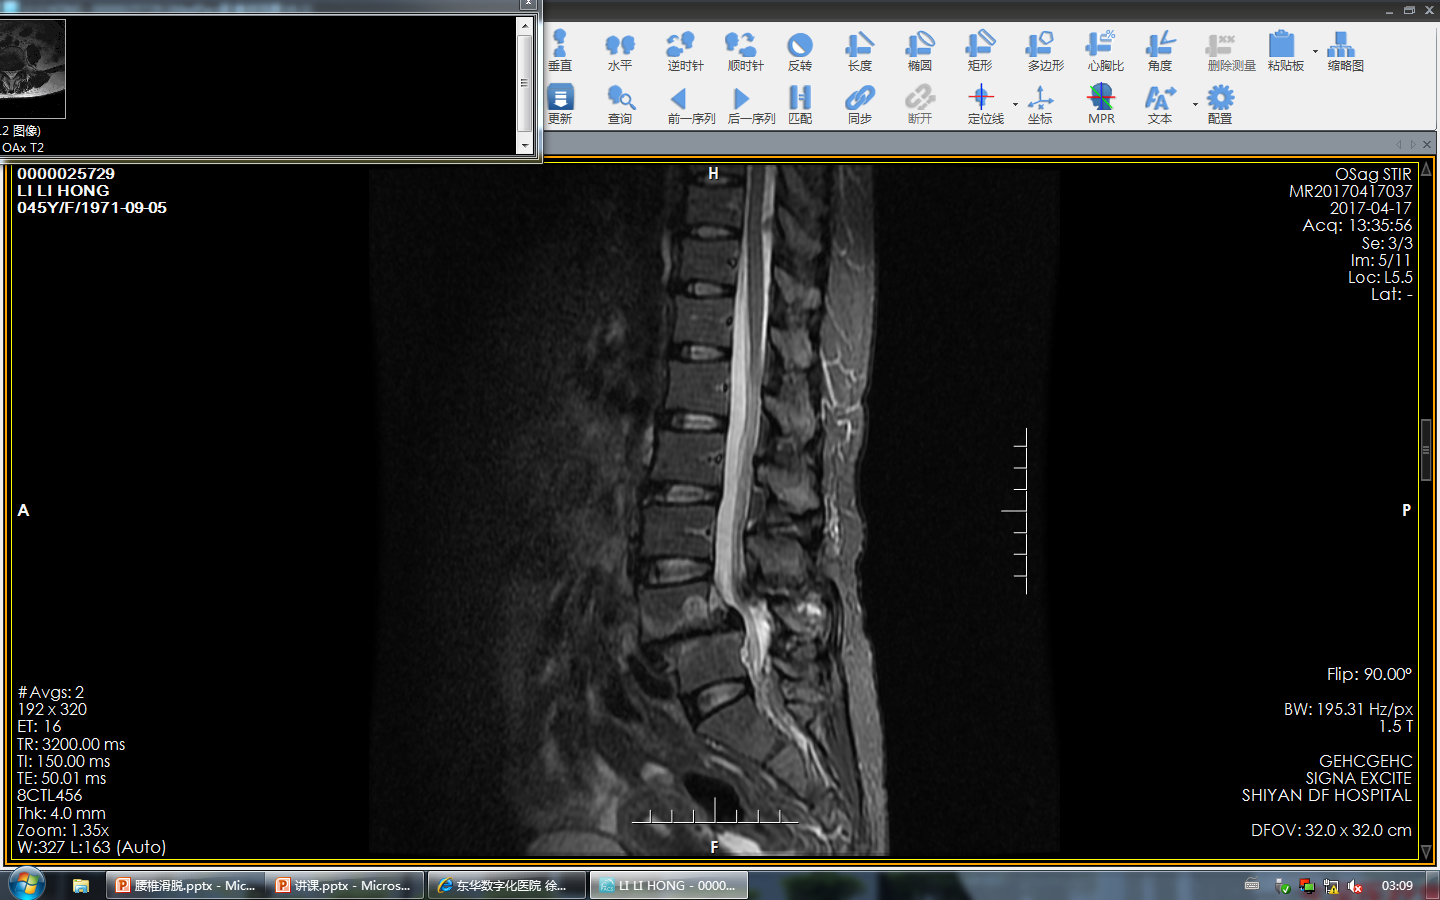

MRI检查:可观察腰椎神经根受压情况及各椎间盘退变程度,有助于确定减压节段和融合范围。

Picture 3